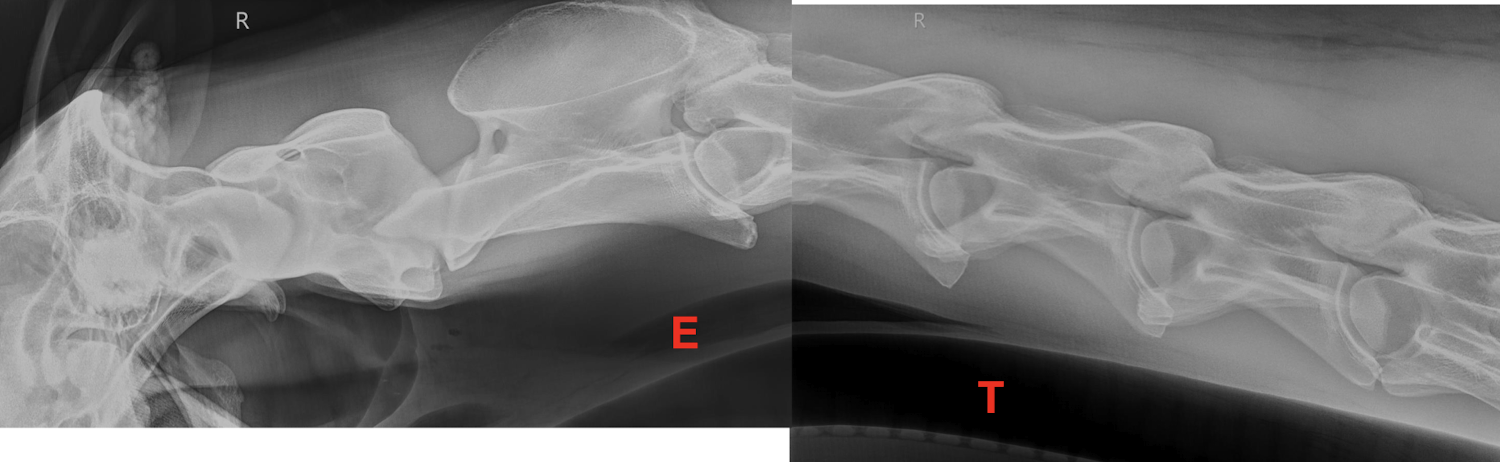

Normal imaging of the neck

What is the purpose of performing a positive contrast esophagram?

To evaluate for esophageal obstructions, strictures, and other lesions.